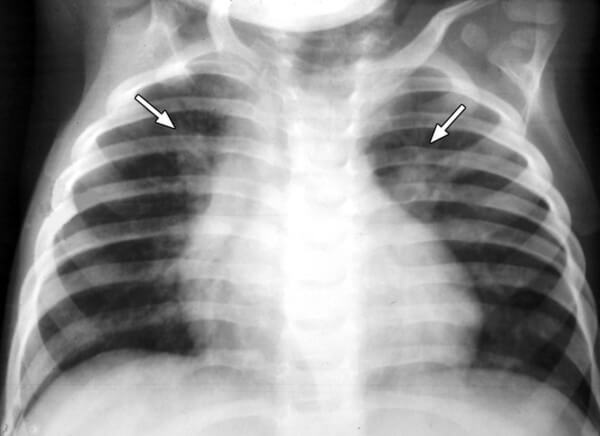

Диагностика пневмонии у детей с помощью рентгена вызывает ряд некоторых трудностей. Связано это с небольшим объемом легочной ткани и большим количеством структурных элементов на маленькую площадь, которая подлежит исследованию. Из-за этого появляется сложность в правильной оценке легочного рисунка, а также диагностирования состояния легочных корней и лимфоузлов.

Самым распространенным признаком пневмонии у детей, которые проявляются на снимках, являются очаговые тени в нижних сегментах легких диаметром 1-2 мм.

На снимке видны отдельные небольшие очаги поражения ( 1-1,5 см), расположенные в одном из легких (при билатеральной форме – в обоих). Заметным в данном случае будет расширение корней легких из-за наполнения жидким экссудатом.

Снимок при очаговой пневмонии

- Очаговая форма. На рентгене отображаются небольшие (1-1,5 см) тени со слабой или умеренной интенсивностью окраски, неоднородной структурой и нечеткими границами. Очаги поражения могут быть единичными или множественными, а в некоторых случаях они сливаются в одно большое пятно. Корни легких расширены, причем нарушения нормального рисунка органа могут сохраняться в течение нескольких дней после выздоровления.